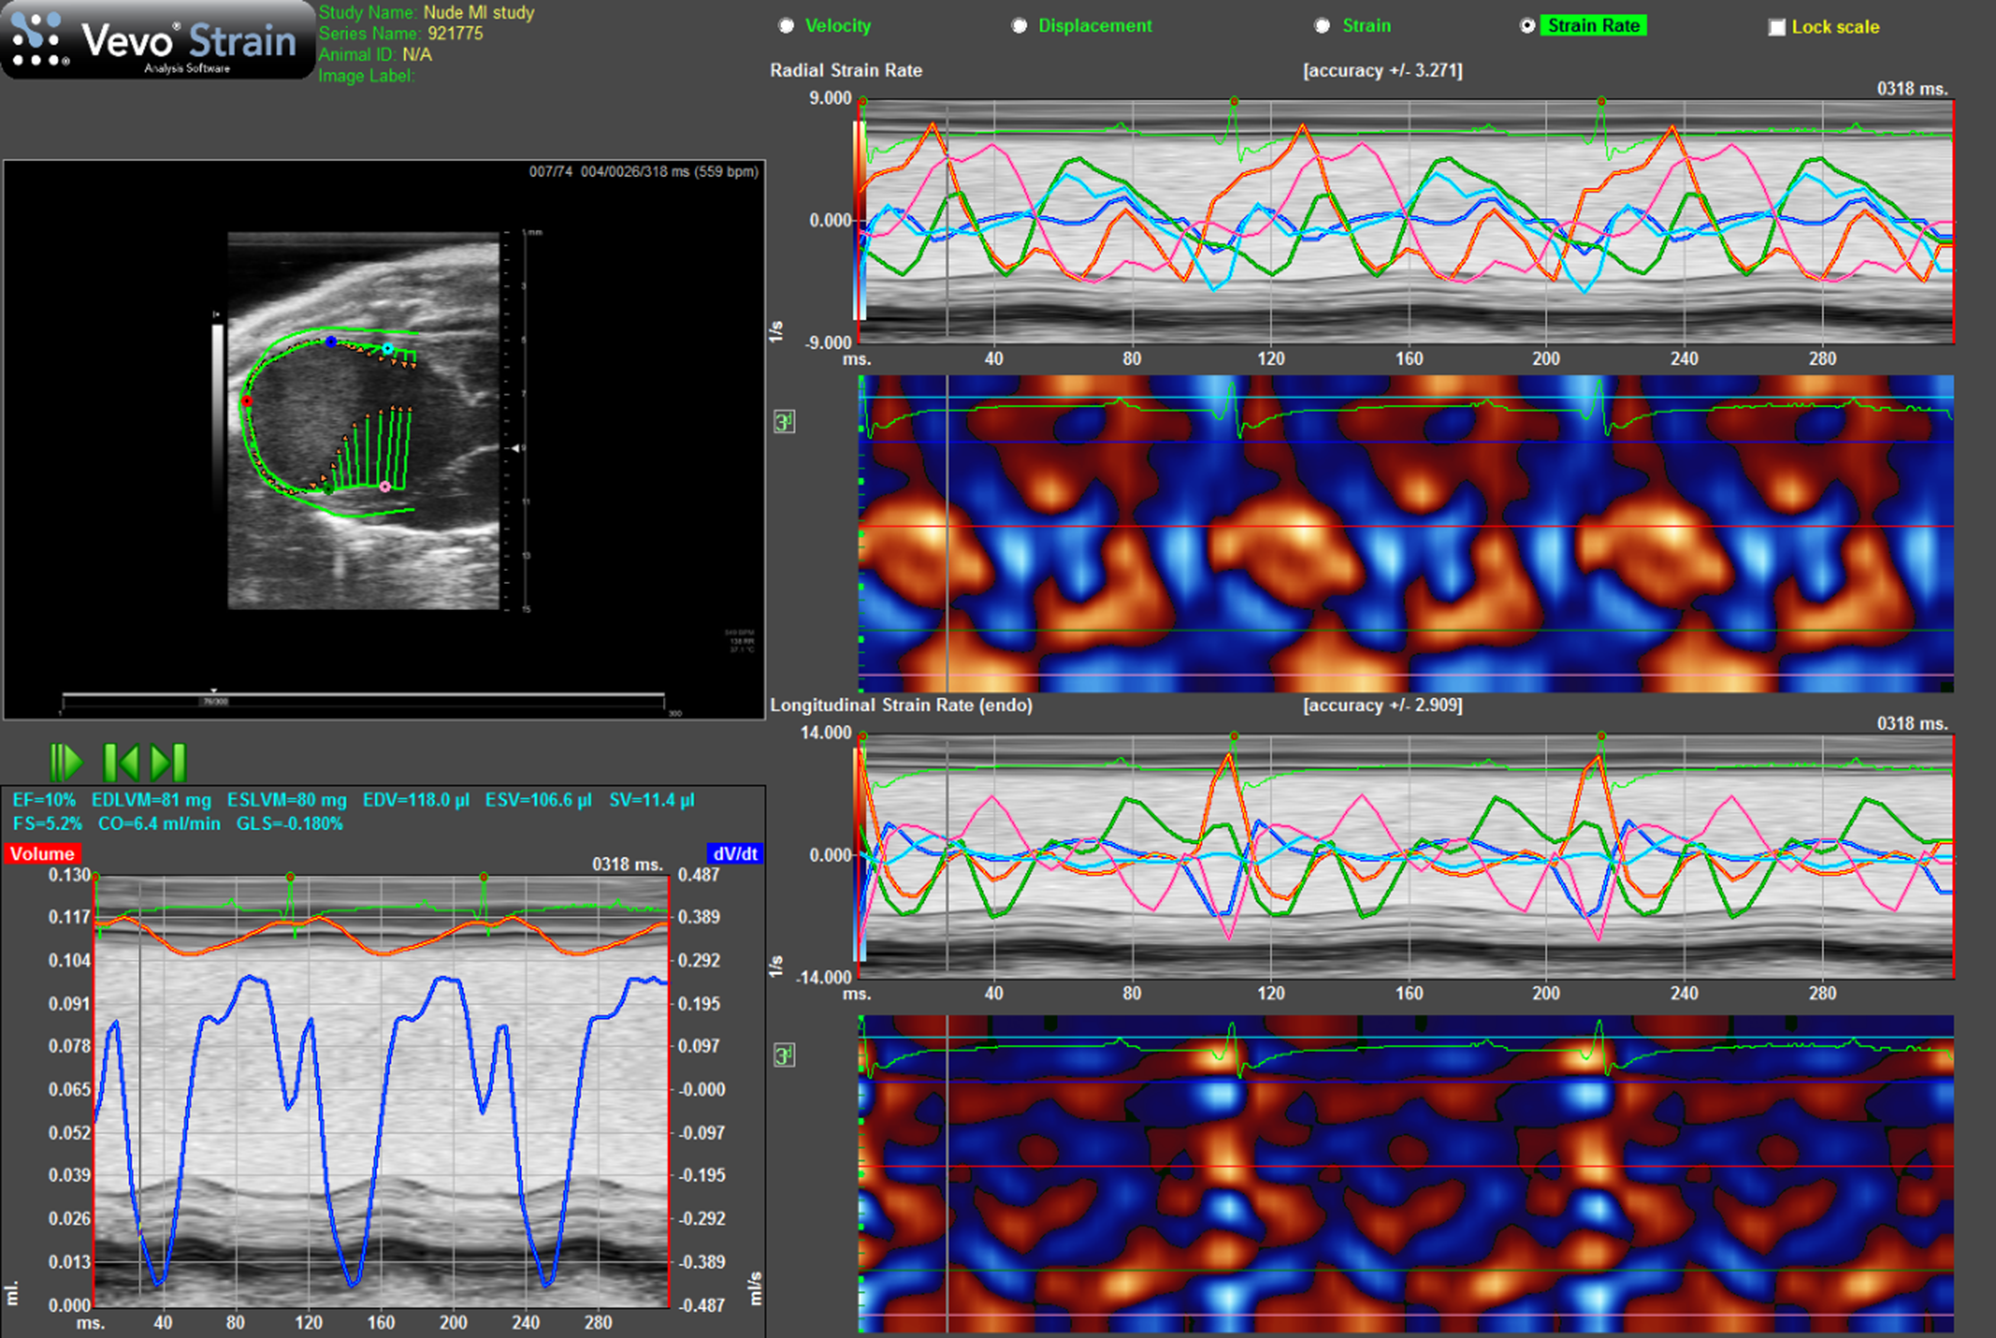

Elastography Techniques

Ultrasound Elastography techniques are used to obtain information on the stiffness of tissue and can essentially be divided into those techniques which measure strain and those which measure shear wave velocity and from that directly measure Young's modulus (stress/strain). Strain elastography involves deformation of the tissue by application of a force (stress) and measuring the resulting degree of compression or extension of the tissue (strain) and comparing this to a reference soft tissue yielding a parameter known as the strain ratio. Since the magnitude of the stress applied is difficult to measure, strain elastography is not an intrinsic measure of tissue stiffness per se but the strain ratio can be used to infer tissue stiffness. Strain-rate is the change of tissue deformation with time. Both strain and strain-rate are routinely used in cardiac applications, where strain and strain-rate values from different regions of the myocardium can be compared. Strain analysis using ultrasound is generally performed using speckle tracking techniques whereby the speckle within different pre-selected ROIs (kernals) is tracked and the relative displacement between the two kernals can be measured. The distance between the two kernals, enables strain to be calculated and the variation of strain over time is strain-rate (s−1) [4] (Figure 7).

FIGURE 7

www.frontiersin.org

Figure 7. Strain rate imaging of a nude mouse with MI as the result of ligation of left coronary artery. Top lhs is long-axis view of heart with arrows indicating direction and magnitude of movement of endocardial border. Bottom lhs shows change in volume of cavity over consecutive cardiac cycles alongside ECG and respiration. Top rhs shows radial strain-rate curves from five points selected on endocardial border while lower rhs shows longitudinal strain-rate curves from the same five points.

Strain and Strain-Rate Imaging

Strain and strain-rate imaging are of specific value in rodent cardiac imaging providing information on regional myocardial deformation. Most commercial scanners use speckle tracking to determine strain (deformation)—by measuring the relative displacement of two kernals to determine strain and its variation over time to give strain-rate. In addition to a global strain parameter, radial, circumferential and longitudinal strain can be obtained providing information on regional segmental myocardial motion and systolic function. The timing of maximum and minimum strain and strain-rate values relative to systole and diastole can provide data on desynchronises between different myocardial regions especially relevant in infarct models (Figure 7) [1214].